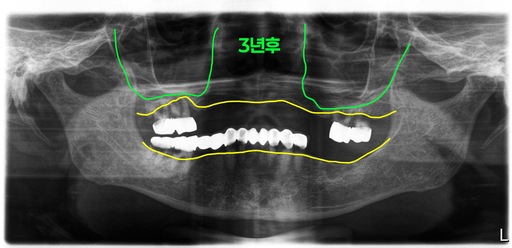

초진시 파노라마 엑스레이입니다. 처음 방문하셨을 때에는 상악에 부분틀니가 불편해서 해결하려고 오셨는데 임플란트 2개 정도 심어서 하는 임플란트 틀니 치료를 원하셨어요.

그래서 당시 환자는 이미 빠진 치아 외에 몇개의 치아에 이차우식과 치주염이 진행되어 빠진부위 임플란트와 문제가 있는 치아만 먼저 치료를 하기로 계획을 세웠습니다.

환자는 3년 뒤에 다시 방문을 하셨습니다. 3년 전에 상담을 하고 치료를 하지 못했는데 입 안 상태가 엄청 나빠져서 오셨습니다.

위에 남아있던 치아들 중 3개는 괜찮았었는데 이제는 4개 모두 발치를 해야 하는 상태였고, 아래도 브릿지 속 치아들이 모두 썩어서 브릿지가 흔들리고 있었어요.

그래서 결국 3년 전의 치료계획대로 치료를 할 수 없는 상태여서 전체 치아를 모두 제거하고 전체임플란트를 하기로 결정했습니다.